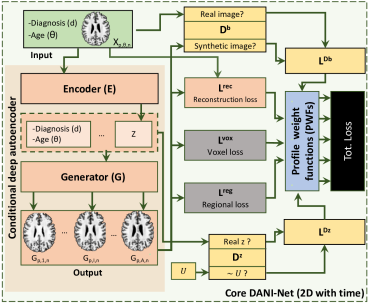

For each axial slice in MNI space, we fit an independent 2D plus time progression model (based on the original DANI-Net [38]). Each DANI-Net model consists of three different sub-blocks (see Fig. 3): a Conditional Deep Autoencoder (CDA) (coloured in pink); a set of adversarial networks (yellow); and a set of biological constraints (grey). We also introduce a novel PWFs strategy for unifying slice models into a 3D progression model during training (blue).

3.2.1 Conditional Deep Autoencoder (CDA)

This block aims to learn a mapping between an initial manifold (representing brain MRI) and a lower-dimensional space, which we refer to as the latent space. This latent space is conditioned on other factors associated with the subject (i.e., current diagnosis, age) to allow manipulation of the image prediction on the original manifold according to these metadata.

More specifically, this block is composed of two deep neural networks: an encoder that embeds in a latent space , and a generator that projects samples in the latent space, back to the original manifold. The latent vector is conditioned on two variables: — a numerical representation [] of diagnosis (cognitively normal CN, subjective memory concern SMC, early/late mild cognitive impairment E/LMCI, Alzheimer’s disease AD); and — an age index binned into groups. This age binning allows learning of morphological changes between age groups and prevents the CDA from memorizing (in the latent space) the age as an individual representation for each sample and thereby overfitting to age.

3.2.2 Adversarial Training

GANs are a class of adversarial deep neural networks that have been successfully used to generate high-quality images across a wide range of tasks.

We introduce a new adversarial training technique for the 4D-DANI-Net. In our case, the generator network (the decoder of our CDA) learns how to create synthetic realistic brain images. Simultaneously, we use two discriminators, and , trained adversarially with the encoder and the decoder of our CDA.

More specifically, is trained to fool , i.e., to generate brain MRI with a similar distribution to the initial true distribution. Simultaneously is trained to discriminate between empirical and synthetic brain MRI (generated by ). To train we use the following loss function:

where is the expectation, estimates the probability that a slice contains a realistic brain and is the latent vector obtained from .

The second discriminator is trained adversarially with the encoder , to produce with a uniform prior and smooth temporal progression. To train we use the following loss function:

where is a vector sampled from and estimates the probability that a vector comes from .

3.2.4 Total Loss

Each single-slice DANI-Net model is computed on the slice position and is trained to optimize all the losses () at the same time. We illustrate this in the black block of Fig. 3.

The total loss is the weighted sum

where and are the cross entropies obtained respectively by the discriminators and , for the slice position over all subjects .